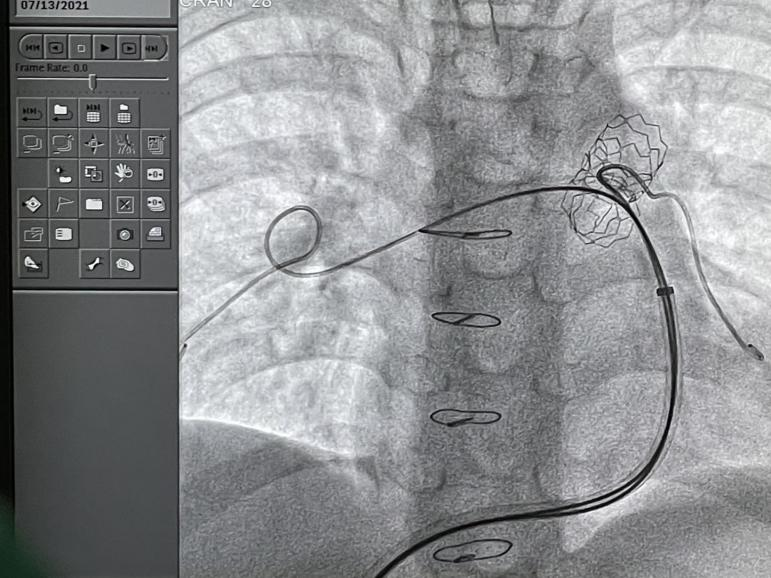

术中造影确认肺动脉狭窄长单21.62mm,狭窄处毗邻血管直径为11.28mm,根据患者情况,选择PAS.S30肺动脉支架。

选择admiral 8mmX40mm球囊进行预扩

沿长鞘将支架送至狭窄处

使用BIB双层球囊,将支架扩张至12mm,与患儿正常血管直径相吻合。